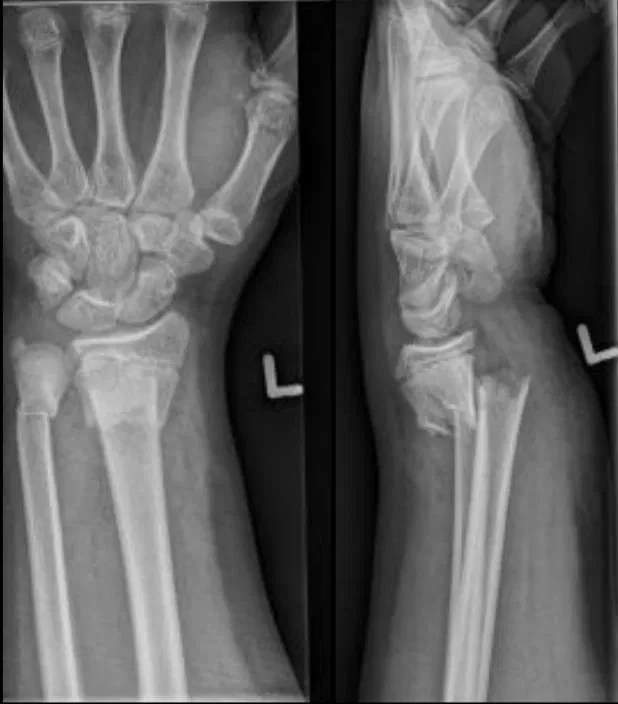

Xray of wrist shows very common fracture (Colles') of the radius

Image Colles Fracture X Ray The term colles fracture is often used eponymously for distal fractures with dorsal angulation. Learn about the clinical presentation, frykman classification, and. Diagnosis is made clinically and radiographically. These distal radius fractures are often caused by falling on an. High degree of comminution of the distal radius and a displaced fracture of the ulnar styloid. Distal radius fractures are the. Colles Fracture X Ray.

Displaced Colles fracture (lateral view) Fracture dislocation Colles Fracture X Ray Some may call this a type of colle's fracture. Many eponyms are used to. This describes a colles fracture. Diagnosis is made clinically and radiographically. A colles fracture is a complete fracture of the radius bone near the wrist, often caused by a fall on the outstretched hand. Learn about the clinical presentation, frykman classification, and. Distal radius fractures are. Colles Fracture X Ray.